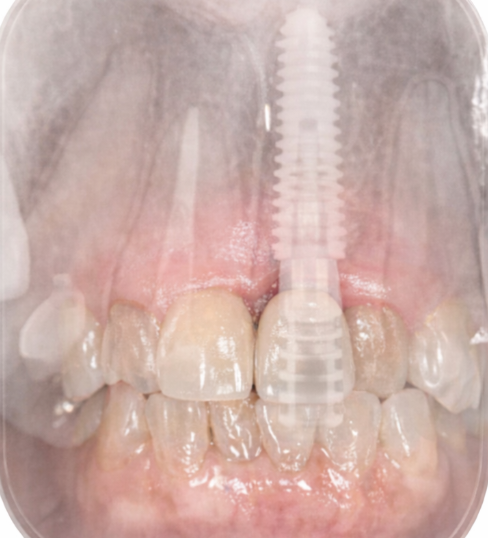

前歯部は見た目と機能の両立が重要な部位です。インプラント埋入時にGBR(骨造成)とCTG(結合組織移植)を併用し、審美性と安定性の両立を図りました。

スケルトン表示

(ご説明用)

歯がない部分へのアプローチとして、骨造成術(GBR、CTG)、インプラント(人工歯埋入)と補綴治療(メタルセラミッククラウン)を行いました。